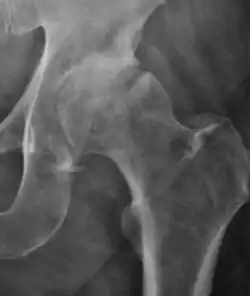

- Slipped capital femoral epiphyses (SCFE)

Slipped capital femoral epiphyses (SCFE) usually affect 11- to 14-year-old adolescents (Figure 4). Radiographs may show widening and irregularity of the physis and posterior inferior displacement of the capital femoral epiphysis. On the AP view Klein’s line, tangent to the lateral aspect of the femoral neck, does not intersect the femoral head indicating that it is displaced. SCFE may compromise the blood supply to the femoral head and cause avascular necrosis, mainly when there is instability between the fragments.[1]

-

Figure 4: (a) X-ray of a 10-year-old child with left hip pain. It was considered normal at emergency despite the widening of the left physis (arrow). Two weeks later epiphysiolysis was evident (b). Despite appropriate surgical reduction (c) osteonecrosis developed and femoral head collapsed 1 month later (d).[1]